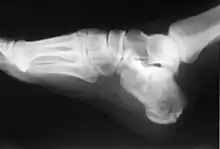

In humans and many other primates, the calcaneus (/kælˈkeɪniəs/; from the Latin calcaneus or calcaneum, meaning heel;[1] pl.: calcanei or calcanea) or heel bone is a bone of the tarsus of the foot which constitutes the heel. In some other animals, it is the point of the hock.

In humans, the calcaneus is the largest of the tarsal bones and the largest bone of the foot. Its long axis is pointed forwards and laterally.[2] The talus bone, calcaneus, and navicular bone are considered the proximal row of tarsal bones.[3] In the calcaneus, several important structures can be distinguished:[3]